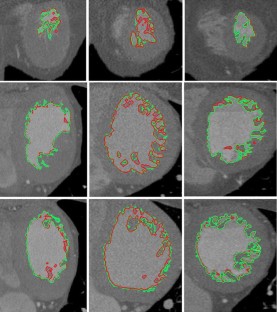

Extraction of the cardiac surfaces of interest from multi-detector computed tomographic (MDCT) data is a pre-requisite step for cardiac analysis, as well as for image guidance procedures. Most of the existing methods need manual corrections, which is time-consuming. We present a fully automatic segmentation technique for the extraction of the right ventricle, left ventricular endocardium and epicardium from MDCT images. The method consists in a 3D level set surface evolution approach coupled to a new stopping function based on a multiscale directional second derivative Gaussian filter, which is able to stop propagation precisely on the real boundary of the structures of interest. We validated the segmentation method on 18 MDCT volumes from healthy and pathologic subjects using manual segmentation performed by a team of expert radiologists as gold standard. Segmentation errors were assessed for each structure resulting in a surface-to-surface mean error below 0.5 mm and a percentage of surface distance with errors less than 1 mm above 80%. Moreover, in comparison to other segmentation approaches, already proposed in previous work, our method presented an improved accuracy (with surface distance errors less than 1 mm increased of 8–20% for all structures). The obtained results suggest that our approach is accurate and effective for the segmentation of ventricular cavities and myocardium from MDCT images.

Figure 3